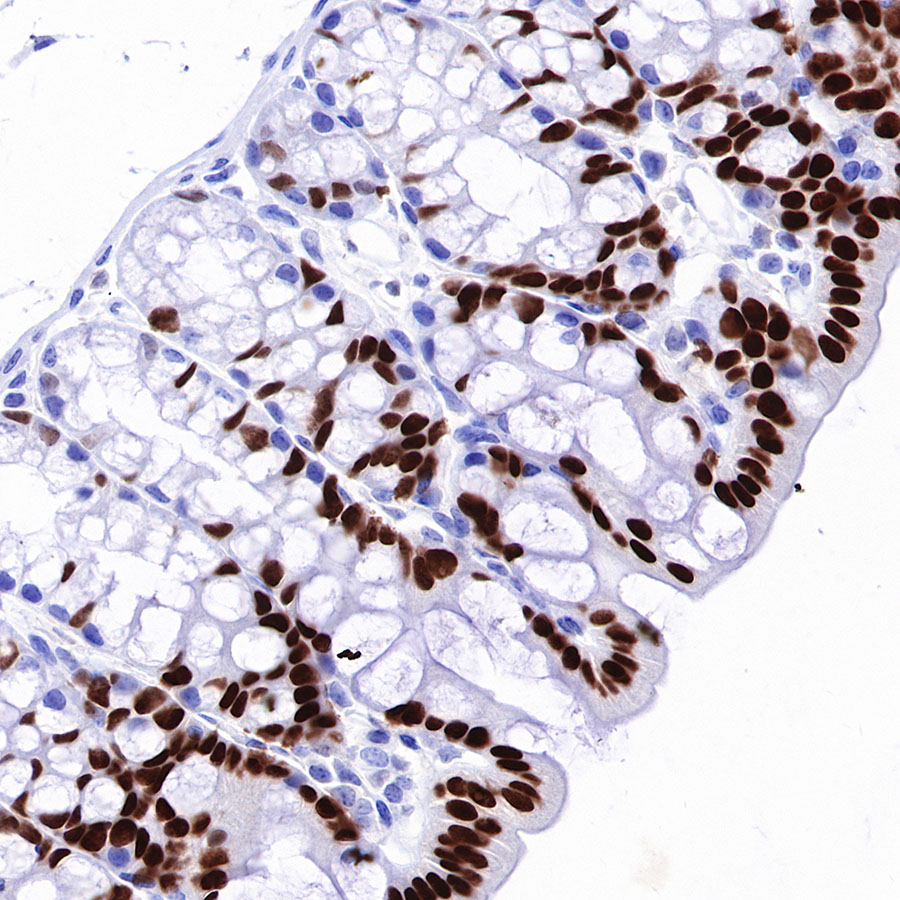

IHC shows positive staining in paraffin-embedded mouse colon. Anti-HNF4α antibody was used at 1/500 dilution, followed by a HRP Polymer for Mouse & Rabbit IgG (ready to use). Counterstained with hematoxylin. Heat mediated antigen retrieval with Tris/EDTA buffer pH9.0 was performed before commencing with IHC staining protocol.

IHC shows positive staining in paraffin-embedded human colon cancer. Anti-HNF4α antibody was used at 1/500 dilution, followed by a HRP Polymer for Mouse & Rabbit IgG (ready to use). Counterstained with hematoxylin. Heat mediated antigen retrieval with Tris/EDTA buffer pH9.0 was performed before commencing with IHC staining protocol.